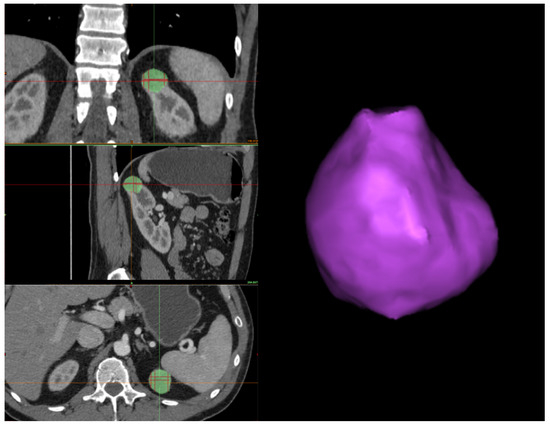

In this Section, we outline the segmentation protocol for obtaining accurate 3D reconstructions of organs and tumors. Our protocol is specific for the reconstruction of kidneys and their associated tumors. The main objective of the protocol is to describe how a human operator should proceed to segment the kidney and the tumor to ensure an accurate reconstruction. Therefore, we structured the protocol into three steps: kidney segmentation, tumor segmentation, and reconstruction refinement. After completing these steps, accurate 3D reconstructions were generated (see Figure 1) and exported as STL files. These files were then provided as input to our algorithm for calculating the CSA.

Therefore, the first step in correcting the reconstruction is to remove any tumor parts mistakenly considered part of the organ during kidney segmentation. Then, the human operator should inspect the interface between the tumor and the kidney to confirm the absence of gaps. If any holes are present, the Fill command is used to address them while checking each slice across the three sections (see Figure 6). Finally, before exporting the 3D models, a smoothing operator is applied to slightly refine the geometries of the two volumes. The final result can be seen in Figure 1, which was obtained from a combination of automated and manual tumor and organ segmentation. As previously discussed, organ and tumor segmentation is fundamental for the algorithm presented in Section 2.2. Here, we described a manual procedure for this segmentation. However, in the future, this could be replaced with a fully automated process.

Figure 1. A 3D reconstruction of a kidney, in yellow, and a tumor, in purple.